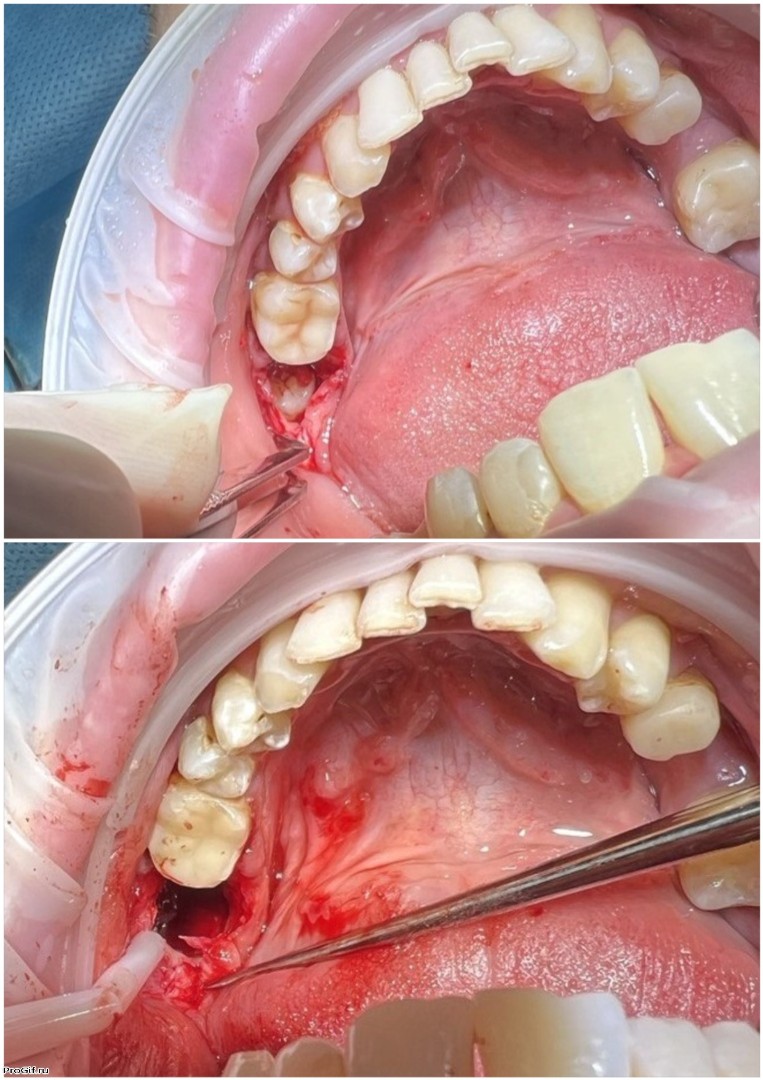

Атравматичное удаление зубов – наиболее безболезненная и щадящая процедура, которая практически не травмирует десну и костную ткань.

Зуб извлекается частями, что позволяет не травмировать окружающие ткани.

В нашей клинике осуществляется удаление самых сложных «зубов мудрости». Обычно удаление зуба под местной анестезией занимает от 10-15 минут, но иногда процедура может занять 30 или даже 60 минут и более.